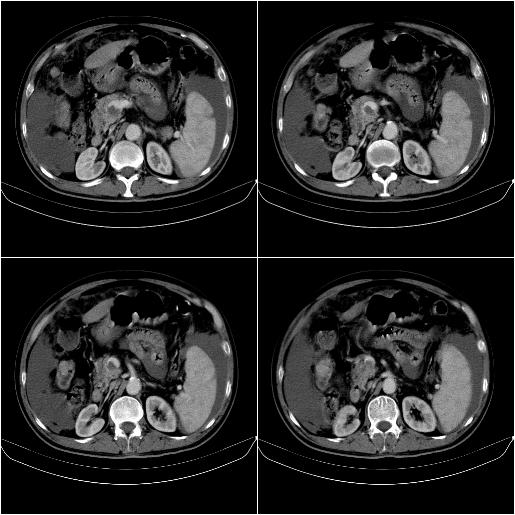

标题: CT21651:M,67Y,肝癌9月,介入术后3月。

m,67y,肝癌9月,介入术后3月。现腹胀、纳差、腹泻。

门静脉有很大的瘤栓,膈肌及膜膜有转移,不用再做了.

情况不好,门静脉癌栓、腹膜转移。

1)肝癌介入治疗术后碘油沉积不良。2)门静脉瘤栓形成,腹膜广泛性转移。3)肝硬化,脾大,腹水。4)慢性胆囊炎。